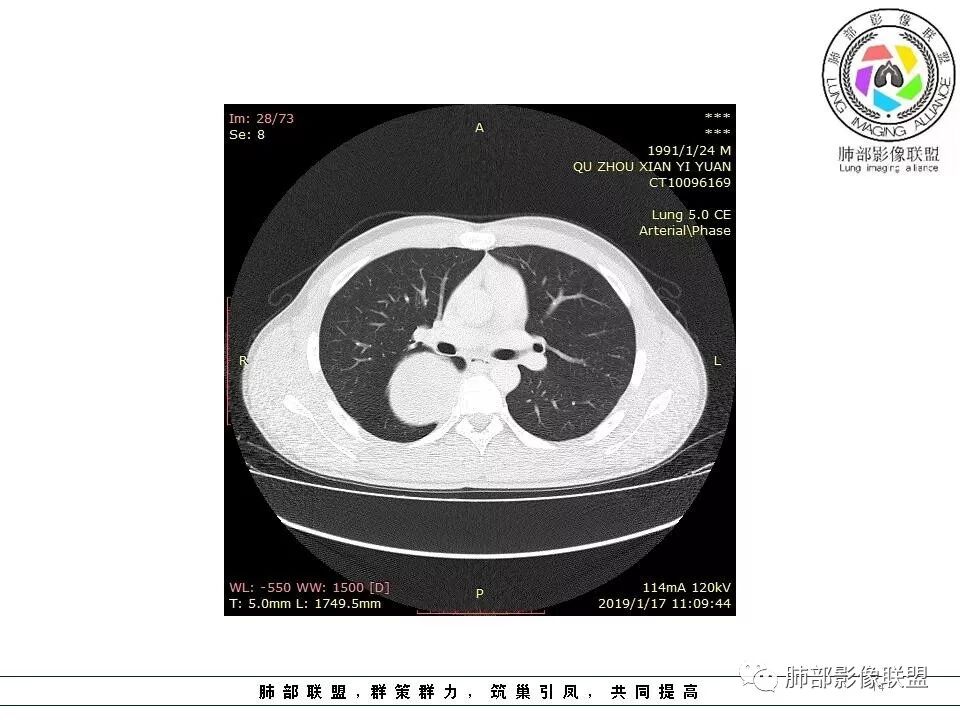

后纵隔脊柱旁占位性病变,疾病谱有神经鞘瘤,sft,节细胞瘤,髓外造血。此例有胸膜尾征,蛇纹征 ,延迟强化。考虑胸膜孤立性纤维瘤。看到有供血动脉,但不知道是哪里的血管。

后纵隔类圆形新生物,边缘光滑,胸膜尾征明显,贴近脊柱,蛇纹,血供丰富,考虑后纵隔软组织肿瘤,具体类型看不出来,鉴别神经鞘瘤。

后纵隔脊柱旁占位性病变,有胸膜尾征,胸膜下脂肪可见,蛇纹征,明显强化。考虑孤立性纤维瘤。

右侧后纵隔脊柱旁占位,边缘光滑清晰,内侧肺组织受压,外侧可见胸膜尾征,增强持续强化,并可见蛇纹血管征。考虑SFT

青年男性,右侧脊柱旁软组织肿块,边缘膨隆,密度不均,临近肺组织受压、胸膜增厚,增强后动脉期呈不均匀强化,并可见肋间动脉供血,延迟期强化较均匀,定位肺外,首先考虑SFT,神经源性肿瘤待排

青年男性,右侧后纵膈肿块,有胸膜尾征,支气管被推压,定位肺外,脏胸膜?血供来自肺动脉及肋间动脉,增强后有强化,蛇纹征,考虑SFT,鉴别鞘瘤

右肺占位,跨越上叶后段、下叶背,边缘光滑,瘤肺界面清,见肺压缩缘(线样不张`强化),见胸膜尾征,胸膜下脂肪未见明显增厚,肋骨丶脊柱未见侵袭及受压,渐进性丶地图样强化,冠状位似见体循环供血

诊断:SFT(来源壁层胸膜?一般小于20%)

鉴别:神经源性(鞘瘤)、LCD、肉瘤丶孤立性间皮瘤

右上肺野脊柱旁软组织肿块,边缘光滑整齐,肺组织及气管右肺上叶支气管受压前移,外移,边缘可见胸膜尾征,病灶内密度不均,增强后渐进性持续强化,其内可见明显蛇纹血管征,首先考虑肺外来源,sft.可能性大

青年男性,瘤肺边界锐利,气管向前推移,定位肺外,局部胸膜增厚,后方见少量积液,提示脏层胸膜来源,增强持续渐渐进性强化,内见蛇纹血管,考虑sft

应该就这两病变鉴别,鞘瘤也可渐进性强化,但鞘瘤囊变多见,内部血管少见不支持

1.右上胸内脊柱旁类圆形肿块,质地似乎比较坚实,密度稍显不均,但未显示明确的坏死。

如此密度形态的病灶位于肺边缘首先应当想到孤立性纤维瘤,可相邻胸膜未见明显的异常强化和胸膜方向延伸。

注意所谓“胸膜尾征”的概念及形成机制与“脑膜尾征”是大不相同的。

3.相邻椎间孔未见扩大,也未见块影延入椎管,易起自于神经根的鞘瘤似乎找不到支持点。

可惜未提供矢状位骨窗图像,如在肋骨内下缘观察到压迹有助于肋间神经的鞘瘤的判断,这是因为二者之间密切的毗邻关系。

4.静脉期轻度不均匀强化,注意不是环形强化,亦未见明确的“AB区”,这点也不支持神经鞘瘤。临床及病灶轻度强化都不支持副节瘤。

尽管神经纤维瘤的诊断确实有些出乎意外,但病例开阔了我们的视野。